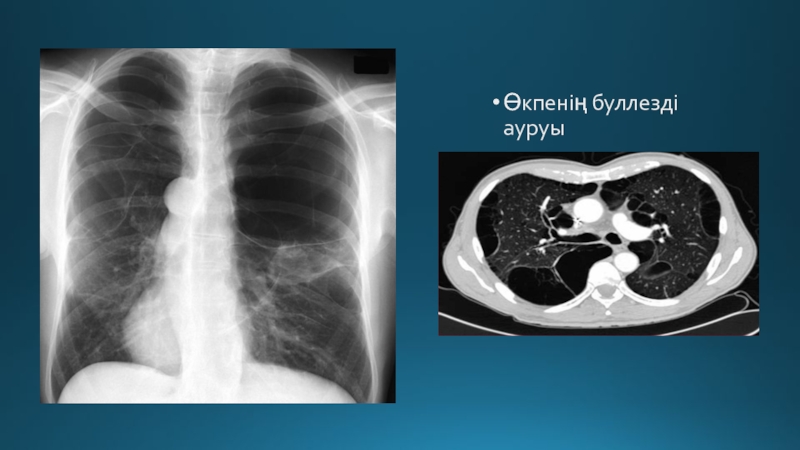

Слайд 55Өкпенің буллезді ауруы

Өкпенің буллезді ауруы

2. Өкпе және кеуде қуысы ағзаларының аурулары:

Бейспецификалық сипатта – өкпенің буллезды ауруында (эмфизема) ауалы кисталардың жарылу салдарынан, өкпе абсцессінің плевра қуысына шығуы (пиопневмоторакс), өңештің кенеттен жарылуы.